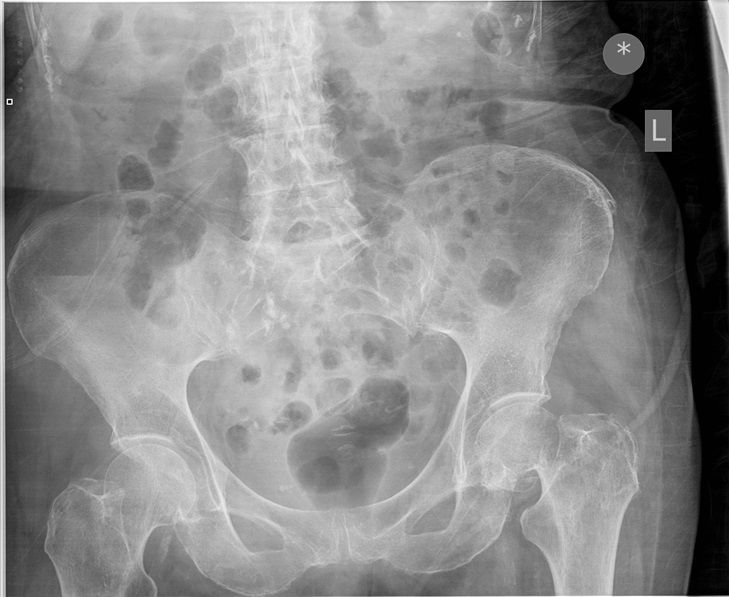

Question 1

Question

Which operation would you chose?

Answer

• THR

• Hemiarthroplasty